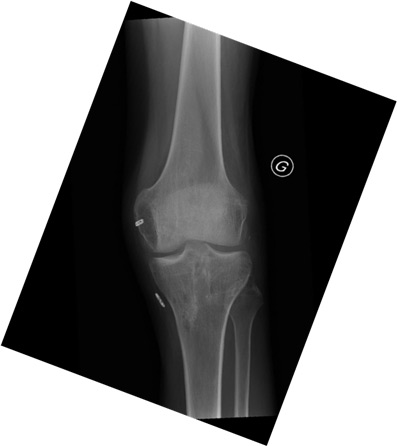

- Knee X-ray: No fractures or bony avulsion